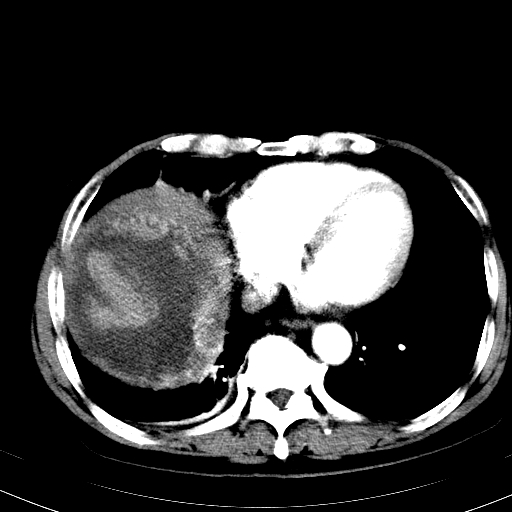

以下是引用hhcckk在2008-6-23 15:10:00的发言:[br]病灶内壁不光滑,中心高密度无强化,考虑肝癌内出血,最后两张横断面是延迟吗?病灶呈低密度。[br][br]鉴别:[br]1、脓肿,内壁光滑,不会发生出血[br]2、血管瘤,早期边缘结节样强化,可合并出血,但延迟后为等密度充填[br]

以下是引用qiuleiyu在2008-6-23 20:53:00的发言:[br]支持;血管瘤伴出血可能大.